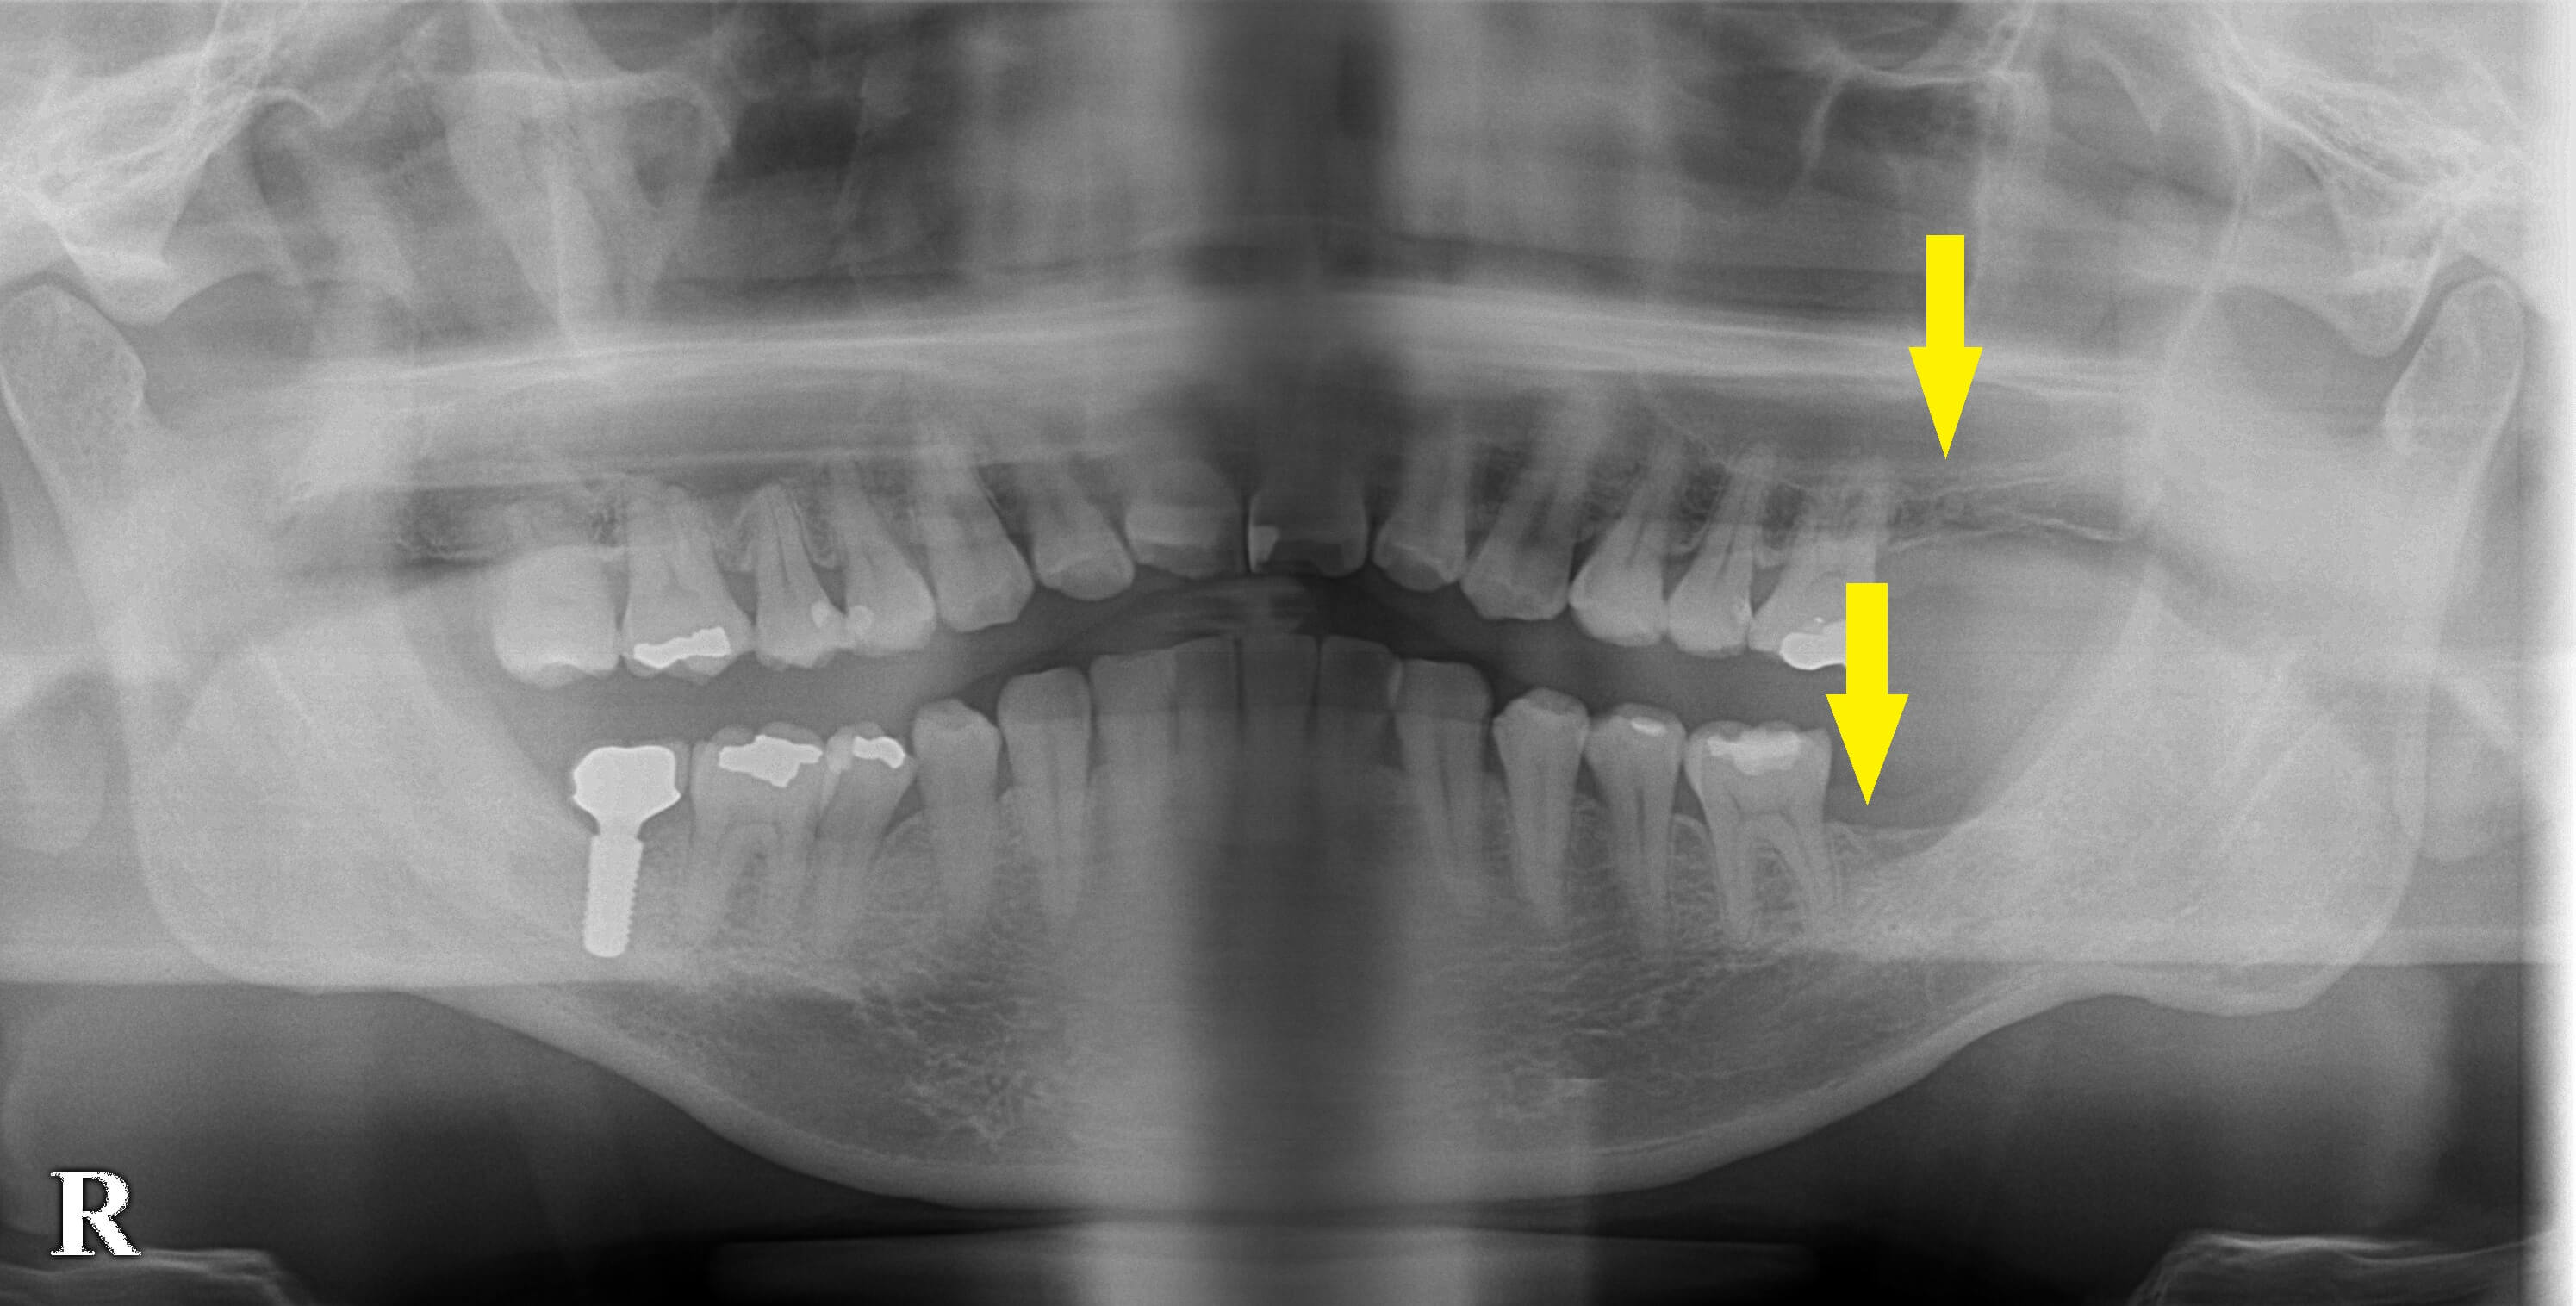

今回左側の上下の第二大臼歯を抜歯され、インプラント治療を希望されたのですが、上顎は骨が薄いので無理と言われ、必要性も低いのでこのままで過ごすことを勧められたそうです。

それでも、患者様はこの歯を回復したいと、強い希望を訴えて相談においでになりました。

下顎はやや短めのインプラントを使用し、上顎はソケットリフトという骨造成を併用すれインプラント治療は可能と説明させていただきました。

この治療方針で了承されましたので、本日インプラント埋入術を施行となりました。